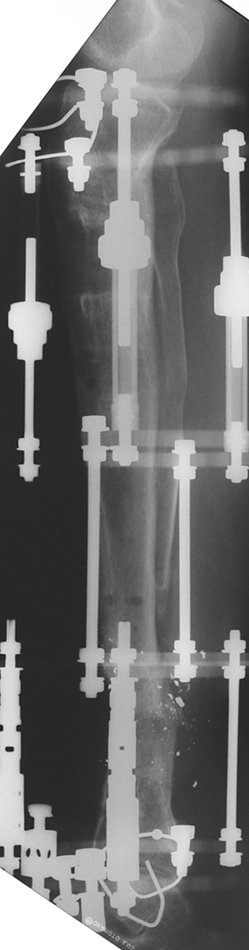

The bifocal compression technique described by Ilizarov, which consists of acute shortening and gradual distraction, allows acute shortening of 4-5 centimeters in tibial defects; defects exceeding this amount can be further shortened gradually by 3 millimeters per day. The same principle is also applicable to the femur, allowing an acute shortening of 8 centimeters. This method facilitates reconstruction of bony continuity and primary or delayed primary closure of soft tissue defects, which would would avoid the requirement for free flaps. A second corticotomy in the metaphyseal region may be used to restore the original length of the shortened bone and to increase it’s vascularity. Intramedullary osteosynthesis of intra-/periarticular fractures is a borderline indication. Open reduction and internal fixation of these fractures hazards the blood supply to (small) bone fragments by extensive dissection, and nonunion or infection is (iatrogenically) invited. In contrary, percutaneous or indirect reduction by limited dissection, small wire and percutaneous cannulated screw osteosynthesis, augmented by external fixation, provides a stable construction to allow early mobilization, range of motion exercises and sometimes partial weight bearing.

My preference in these cases is to use circular external fixators, which are modular, permit fixation of small reduction wires to the frame, and enable postoperative angular adjustments. Recently, combined techniques using external fixators and intramedullary rods have been introduced. The advantage of this method is to decrease the external fixation time by about 50% and to enhance the patient’s comfort.

Case 2